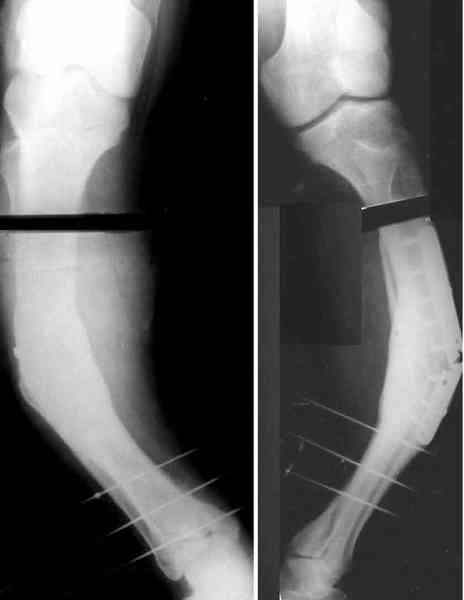

Для продолжения темы - несколько картинок.

Пациент 30 лет, лет пять назад оперирован по поводу перелома голени пластиной. Находясь на героине, нарушил режим, пошел, сломал и ногу и

пластину, но перелом сросся.

В приложении - внешний вид и рентген.

Мнения?

a> В приложении - внешний вид и рентген.

a> Мнения?

AC> Аппарат с шарнирами, чрескожная остеотомия, устранение угла.

Александр, как раз уровень остеотомии подробнее - на вершине деформации? Там Сломанная пластина.

Там не винты (может, плохо видно), а сломанная пластина, вросшая в кость.

a> Александр, как раз уровень остеотомии подробнее - на вершине

a> деформации? Там Сломанная пластина.

Ну, например, на уровне перелома пластинки. Можно пересечь часть кости, не прилежащую к пластинке, затем надломить остальное.

a> Там не винты (может, плохо видно), а сломанная пластина, вросшая в

a> кость.

Пластинку и винты мне удалось разглядеть только на профильной проекции, точнее, трехчетвертной, судя по виду коленного сустава (правый снимок). На фасной - вообще не могу разобрать, где она :( Но, в конце концов, можно и не видя ее сказать, что уровень остеотомии может быть и другим, ниже или выше пластинки, придется только компенсировать смещение по ширине, которое появится при полном устранении угла не на вершине.